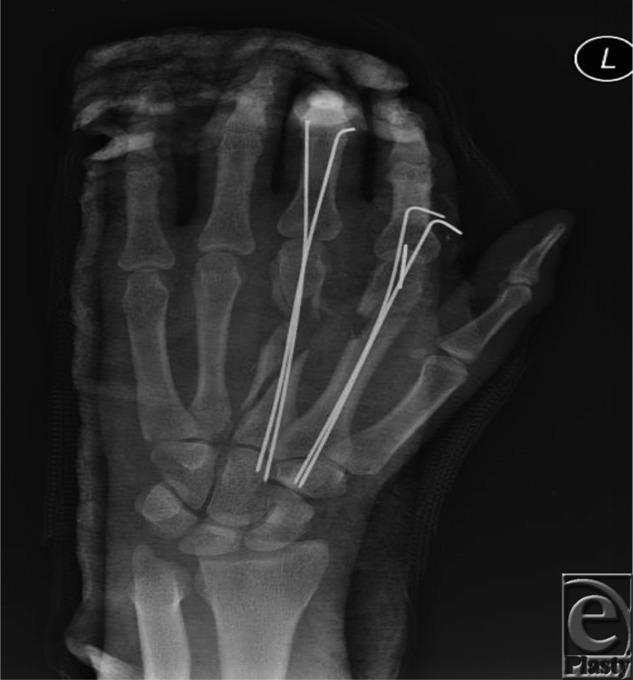

Reconstruction of a Complex Metacarpal Shaft Fracture With Segmental Bone Loss Using Autologous Iliac Crest Bone Graft.

Eplasty. 2015 Aug 20;15:ic47. eCollection 2015.

https://cdn.ncbi.nlm.nih.gov/pmc/blobs/372c/4545955/82e42d610772/eplasty15ic47_fig2.jpg

https://cdn.ncbi.nlm.nih.gov/pmc/blobs/372c/4545955/e1afd82abbb9/eplasty15ic47_fig3.jpg

https://cdn.ncbi.nlm.nih.gov/pmc/blobs/372c/4545955/12051dc2a376/eplasty15ic47_fig1.jpg